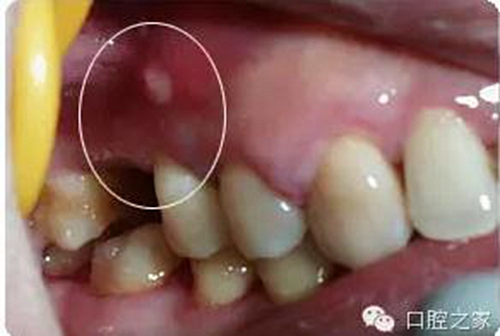

臨床上有的病例雖經(jīng)規(guī)范的根管治療,但臨床癥狀仍未能改善,有的經(jīng)過(guò)多次封藥仍有膿血液等滲出;有的久治叩診痛仍不消失;有的竇道口溢膿雖經(jīng)多次封藥仍無(wú)改善等,因而未能達(dá)到根管充填的基本要求。和田甫等將治療5次以上癥狀未能改善的稱(chēng)為難治性病例,并將根管擴(kuò)大困難及防濕困難病例亦列入。筆者認(rèn)為,真正的難治性病例只有前者;因?yàn)楹笳呖赏ㄟ^(guò)其它方法加以補(bǔ)償或克服。例如根管擴(kuò)大困難,可以通過(guò)增加封藥次數(shù)或封入具有滲透性強(qiáng),并有殺菌解毒作用的藥物治療,仍可獲得良好的效果;而隔濕困難則可使用橡皮樟或四手工作法克服。

根管內(nèi)因素治療失敗,查清原因后重新治療,大都可以治愈。根管外因素所致失敗,除部分病例配合外科可以治愈,大多數(shù)病例重新作根管治療也難以成功,形成真正的難治性根尖周炎。筆者在《實(shí)用牙髓病診療學(xué)》中將竇道口形狀分為6種,其中的膿性針眼狀竇口(壓有白色膿液溢出,竇口僅有針眼大小無(wú)突起)幾乎都是根管外原因,單純根管治療難以奏效。